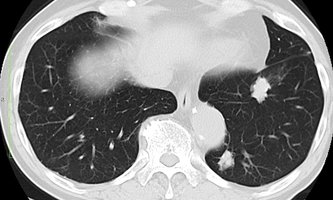

肺がん診療など呼吸器強化、岐阜・松波総合病院に呼吸器センター新設 外科専門医増、AIも導入